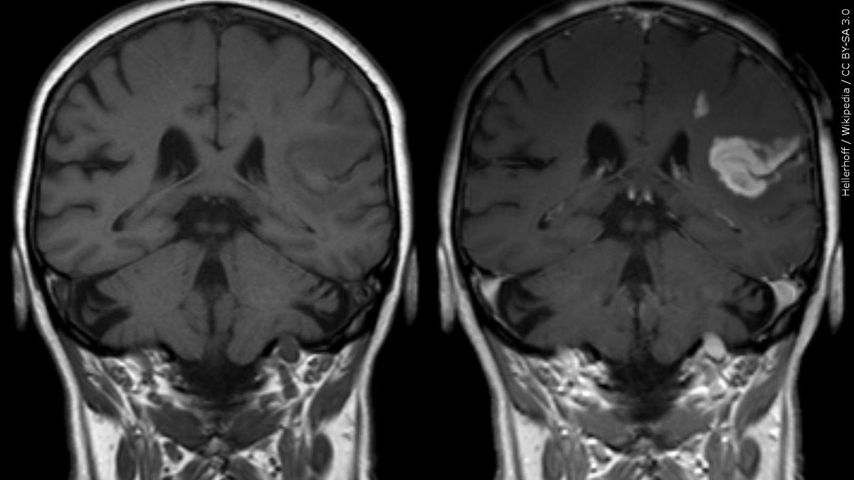

A concussion can happen after a hit to the head, a neck injury or even a whiplash injury, where the head is jolted but not hit. Doctors say that every concussion is unique. Symptoms vary, but kids may complain of not feeling right, they may be more irritable, forgetful or slow responding to questions. If a parent is concerned, it is important to remove a child from an activity right away to prevent further injury.

A concussion is a traumatic brain injury and should never be taken lightly. A child should not return to their spot until they are symptom-free and cleared by a medical professional.